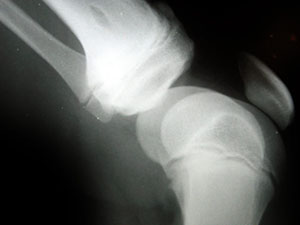

Knee arthritis is a painful condition in which the joints in the knee become inflamed. Depending on the severity of the condition, it may limit an individual’s normal range of motion, forcing him or her to keep body weight off the affected knee. While there’s no known cure for arthritis of the knee, a recent study found herbal acupuncture to effectively treat the symptoms associated with this condition. continue reading